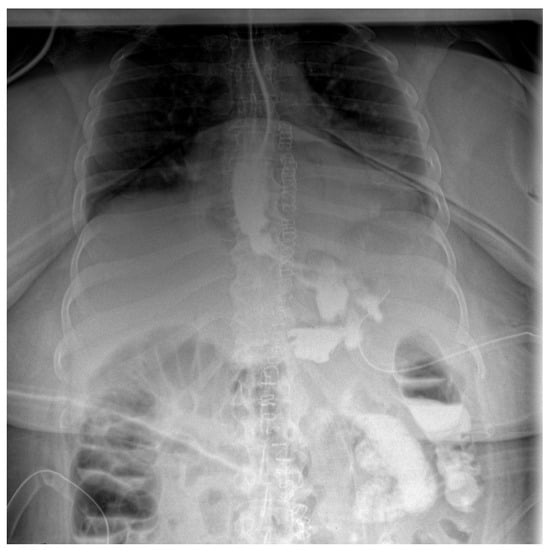

The postoperative course remained favorable (Figure 4 and Figure 5), allowing the medical team to discharge the patient after 51 days with specific recommendations.

Figure 4.

Contrast-enhanced abdominal radiograph demonstrating complete resolution of the fistulous tract, with no contrast leakage or communication visible.